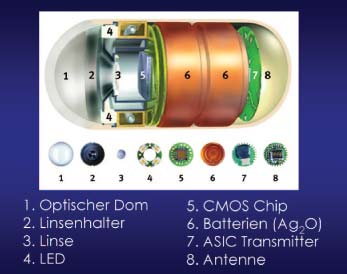

In den 90er Jahren suchten unabhängig von einander zwei Forschungsgruppen in Grossbritannien und Israel einen Weg mittels Radiofrequenztechnik den Dünndarm mit geschluckten «Wanzen» zu untersuchen. Was 1997 in einem lockeren Kooperationsgespräch begann, führte schon im Januar 2000 zur gemeinsamen Erstpublikation der Methode in Nature, der weitere Kurzkommunikationen in klinischen Zeitschriften folgten [1-3]. Die Methode ist bestechend: Weitwinkeloptik, Lichtquelle, Chip, Sender, Antenne und Batterie wurden auf die Grösse einer Vitaminkapsel minimiert:

Auf der Haut angebrachte Elektroden empfangen die von der Kapsel ausgesendeten Signale und speichern sie fortlaufend in elektronischer Form. Bei einer Frequenz von 2 Bildern pro Sekunde und einer Batterielebensdauer von etwa 8 Stunden werden so über 50000 konsekutive Einzelbilder gespeichert, die nach Übertragung auf einen PC als kontinuierlicher Film betrachtet werden können. Während der Untersuchung wird die zum Einmalgebrauch konzipierte Kapsel durch die normale Peristaltik bewegt und, nach Aufbrauchen der Batterie funktionslos geworden, auf natürlichem Weg ausgeschieden. Dabei ist der Patient so mobil wie bei der Aufzeichnung eines 24-Stunden EKGs.